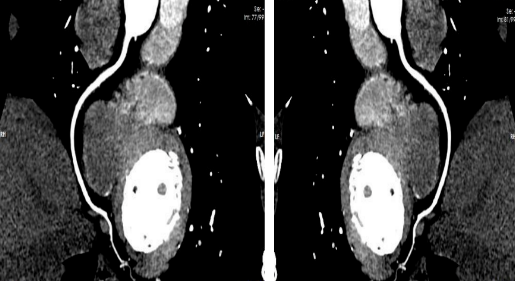

此种方法是将造影剂通过静脉途径以 4-6ml/s 的速度输入患者体内,利用人工智能、软件智能跟踪及心电门控等技术,对冠状动脉及其分支,心脏室壁运动等进行清晰显示。与传统冠脉造影相比,冠脉 CTA 对于冠脉开口变异,能更好地显示血管的开口情况,更好地确定冠脉斑块的性质, 并能显示冠脉以外的病变:如心肌桥、肿瘤等,对心脏和大血管解剖结构的显示优良。

CT具有成像速度超快、图像清晰的优点,能够开展各器官脏器平扫、增强检查、全身血管造影剂灌注成像检查,具有二维、三维等多种重建技术及丰富的影像后处理软件;能够开展CT全身血管成像、冠状动脉血管成像、全身多部位大血管联合成像、胸痛及卒中一站式检查、全身多脏器血流灌注成像,能谱CT成像,达到对冠心病、急性脑卒中、心肌梗死等疾病的早期诊断。熟练开展CT引导下的穿刺活检、CT引导下腰椎间盘突出症臭氧消融治疗术。